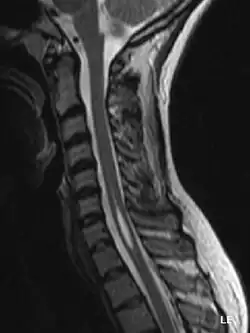

MRT-Aufnahme: Die Höhlenbildung im Rückenmark ist gut zu erkennen

Die Syringomyelie (von altgriechisch σύριγξ syrinx, deutsch ‚Rohr, Flöte‘ und νωτιαῖος μύελος nōtiaios mýelos, deutsch ‚Rückenmark‘) ist eine röhrenförmige Höhlenbildung in der Grauen Substanz des Rückenmarkes. Synonym wird auch von Hydromyelie (von ὕδωρ hydor, deutsch ‚Wasser‘) oder der Kombination beider Begriffe von Hydrosyringomyelie gesprochen.